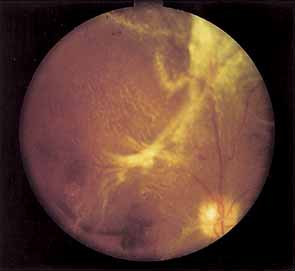

Proliferative vessels usually arise from veins and often begin as a collection of fine vessels. When they arise on or within 1 disc diameter of the optic disc they are referred to as neovascularization of the disc (NVD) (Fig. 9). When they arise further than 1 disc diameter away, they are called neovascularization elsewhere (NVE) (Fig. 10). NVE nearly always grows toward and into zones of retinal capillary nonperfusion, but capillary nonperfusion is nearly always more widespread in eyes with NVD than it is in NVE.12 Interestingly, it is seen more often in patients younger than 40 compared to older patients with diabetes.13

Fig. 9 Advanced neovascularization of the disc.

Fig. 10 Neovascularization elsewhere (NVE).

Once the stimulus for growth of new vessels is present the vessels grow along the path of least resistance. The absence of the internal limiting membrane over the optic disc could explain the proclivity of new vessel growth at that location. Neovascularization grows readily along connective tissue scaffolding such as the posterior hyaloidal face (Fig. 11).